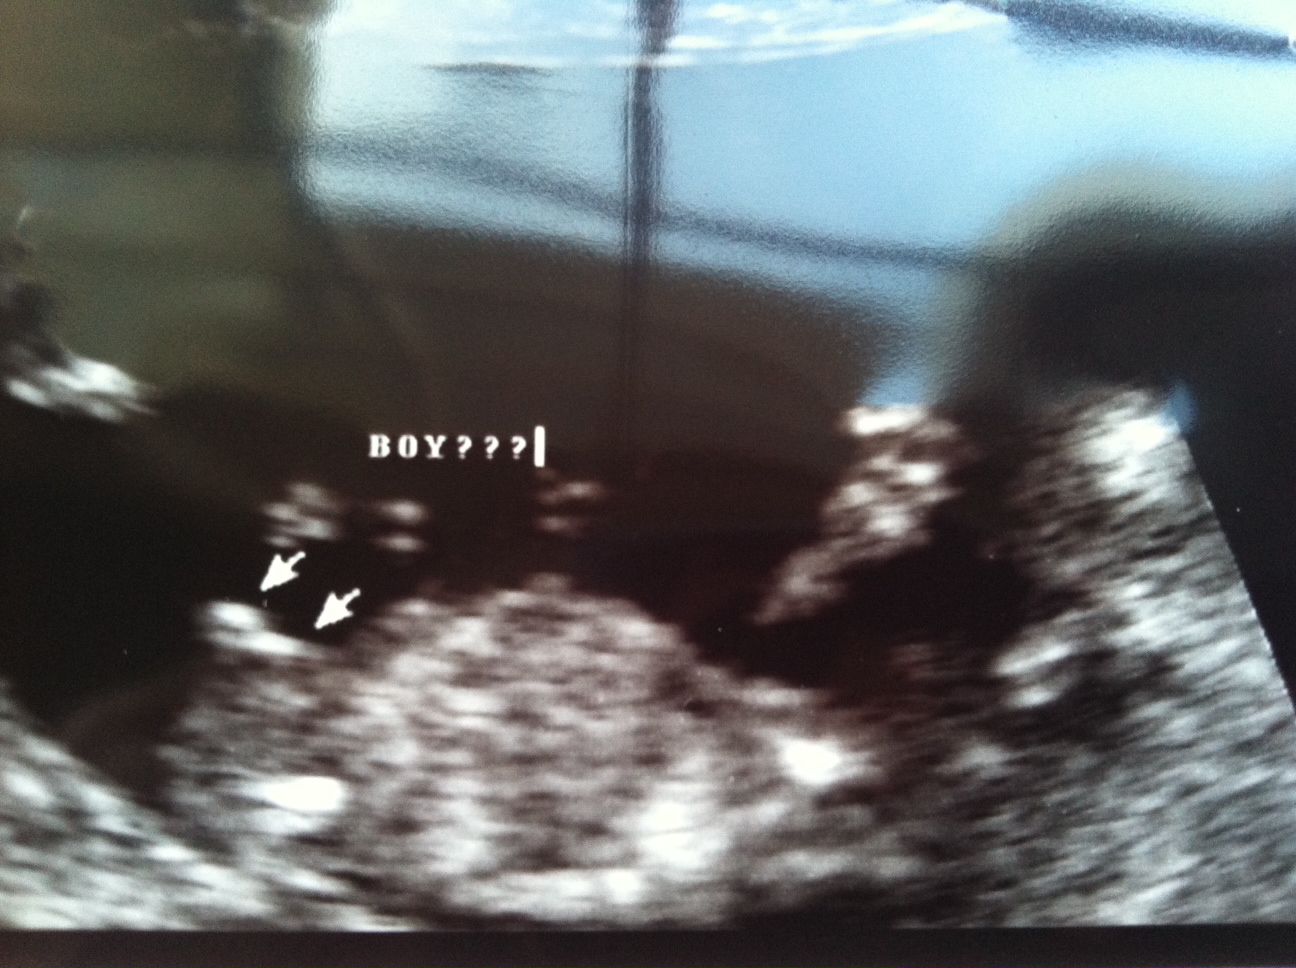

12 sonogram- 2 techs guess boy, 2 techs guess girl

This is not my baby, but I told my SIL that I would post her pic to see if I can get any guesses.

She was 12 weeks exactly when this picture was taken. Two techs were with her during the scan and they told her they thought maybe boy, then futher into the scan changed their minds to thinking girl, then went back to guessing boy. But their boy guess was still without certainty.

Then two other techs looked at this picture and thought it leaned a little more toward being a girl...said they felt the nub was more in line with the spine. But they also agreed, this one was tricky. T

Any guesses? Thanks!